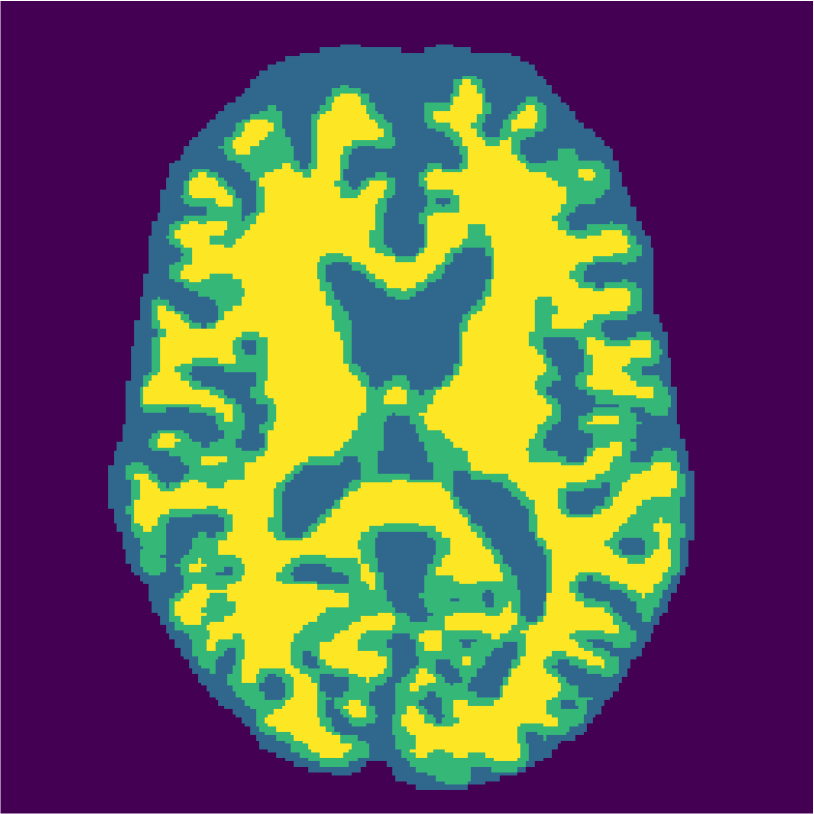

Appendix A describes the nuclear magnetic resonance (NMR) relaxation times for the tissues in the Brainweb anatomical models, for 1.5 and 3.0 Tesla field strengths. The tissues in the anatomical models are grouped into ”background” (BKG), ”cerebrospinal fluid” (CSF), ”gray matter” (GM), and ”white matter” (WM) to compose the ground truth segmentation labels for the simulated scans. The simulations result in images of 256 by 256 pixels, with a 1.0x1.0mm resolution. Figures 5(a) and 5(b) show examples of the Brainweb1.5T and Brainweb3.0T scan of the same subject. For all scans, we used a brain mask to strip the skull.

Figure 6 displays the manually selected patches and their position within the image. For both the source and target classifier, one target patch per tissue is insufficient to achieve good tissue classification performance (2 (top row): 0.631 and 0.613). However, the mrai-net classifier shows considerably better performance (0.223), using only one target patch per tissue. The proxy -distance also drops from near perfect separability (1.88) to near invariance (0.26). Randomly selecting (10 repeats) 1 target patch per tissue (Table 2 (bottom row)), shows worse performance of the mrai-net classifier, for both the classification error (0.250) as well as the -distance (0.41). Suggesting that purposive (information rich) sampling beats random sampling in this case.

Examples of the segmentation results on one of the target test images are shown in Figure 8 for experiment 2.1, Figure 9 for experiment 2.2, and Figure 10 for experiment 2.3. Examples are shown after using 1 target patch per tissue for training, and after using 100 target patches per tissue for training. The results show that only the mrai-net classifier is able to predict a segmentation that approaches the ground truth with only 1 target patch per tissue for training (error for experiment 2.1 = 0.269, experiment 2.2 = 0.403, experiment 2.3 = 0.320), while the source and target classifiers cannot (source error for experiment 2.1 = 0.667, experiment 2.2 = 0.653, experiment 2.3 = 0.435; target error for experiment 2.1: 0.591, experiment 2.2: 0.614, experiment 2.3 = 0.596). After using 100 patches the source and target classifiers can predict a gross segmentation of WM, GM and CSF (source error for experiment 2.1 = 0.213, experiment 2.2 = 0.384, experiment 2.3 = 0.363; target error for experiment 2.1: 0.205, experiment 2.2: 0.368, experiment 2.3 = 0.368), but the mrai-net classifier prediction shows more details and a lower tissue classification error (error for experiment 2.1 = 0.111, experiment 2.2 = 0.276, experiment 2.3 = 0.284).